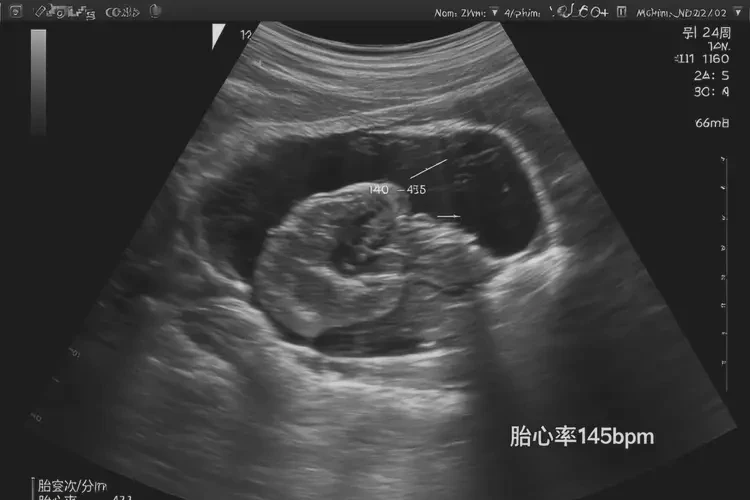

胎心率77次/分钟对于孕24周4天的胎儿来说明显偏低,通常正常胎心率应在110-160次/分钟之间。

在孕24周4天时,胎心率仅为77次/分钟,这通常被视为异常情况。正常情况下,胎心率应保持在110-160次/分钟的范围内。如此低的胎心率可能表明胎儿存在健康问题,如缺氧或其他心脏功能异常。是否需要保胎需要综合考虑多种因素,包括胎心率的持续情况、胎儿的其他监测指标以及医生的专业评估。

- 在孕24周左右,正常胎心率应保持在 110-160次/分钟 之间。